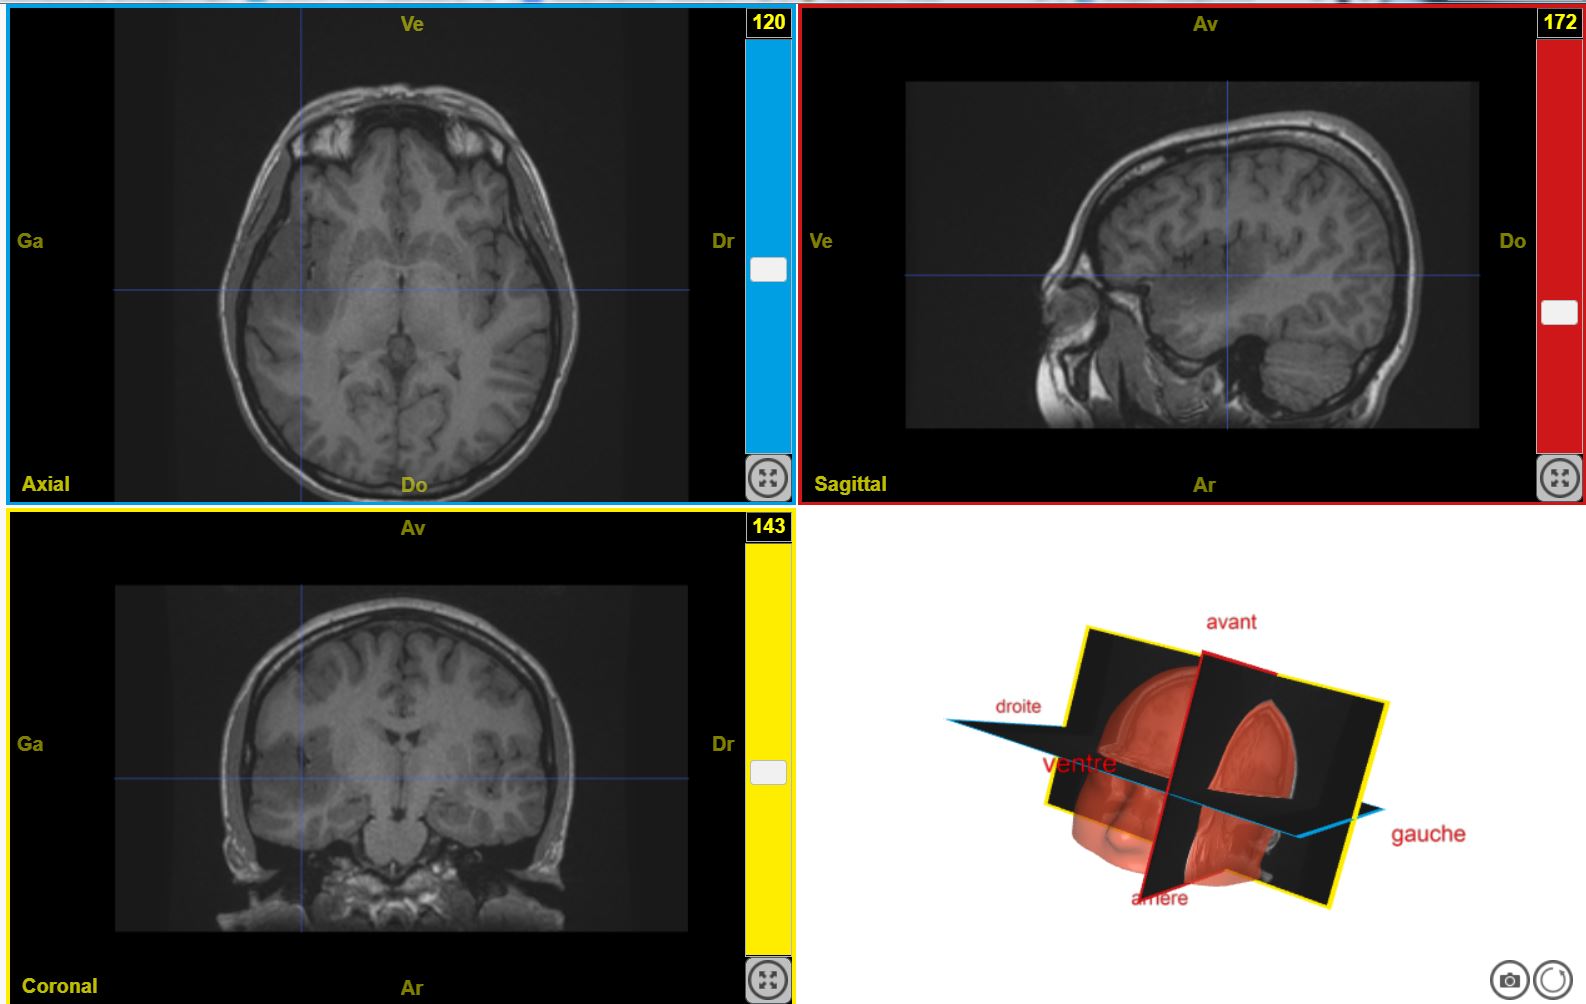

TumeurHallucinationAuditive T1